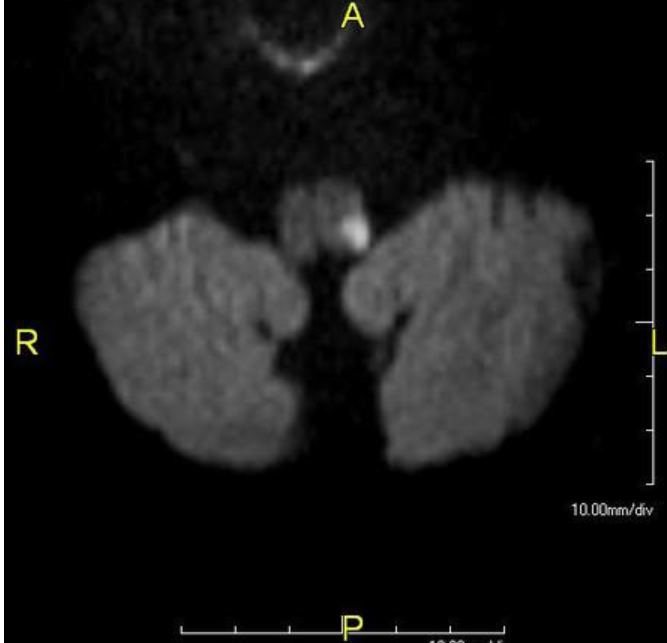

Patient with left sided ptosis has this MRI

What other features would you suspect? (8)